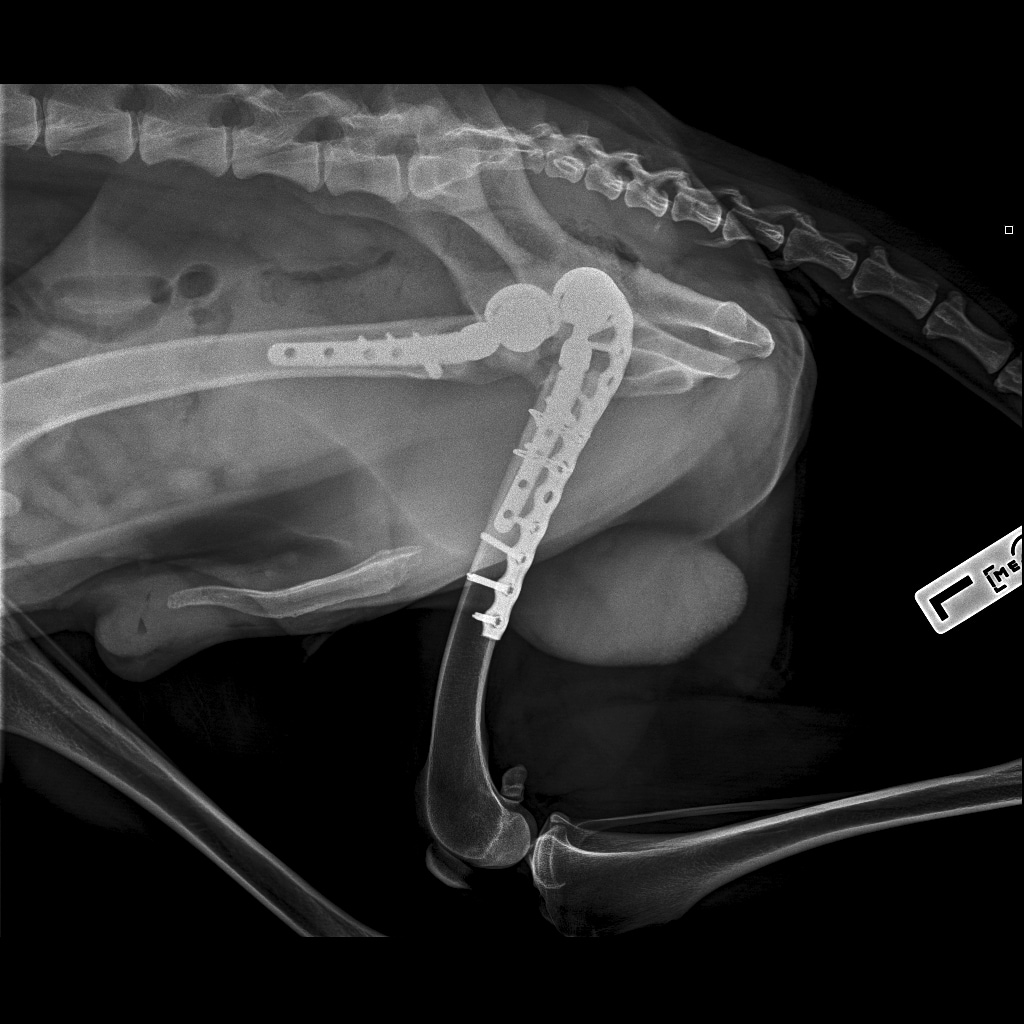

Вчера резко захромал, встал на 3 ноги и понос.

По рентгену чисто

В понедельник КТ